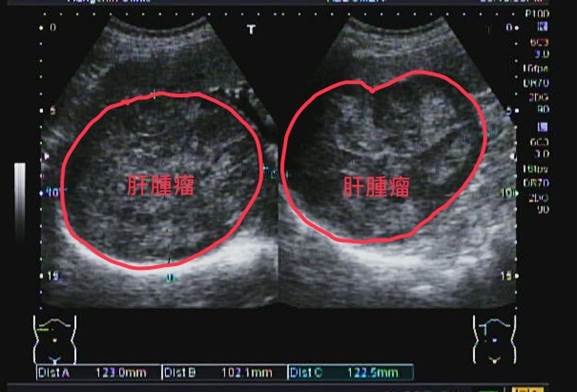

超音波揪出沉默的肝腫瘤

75歲先生因腹脹胃酸至診所就診

問診後發現最近體重明顯下降且大便習慣改變

故安排了腹部超音波及糞便檢查

腹部超音波下發現一顆巨型肝腫瘤

故轉診至醫院進一步檢查醫院安排了電腦斷層:

電腦斷層後確認為肝癌

肝癌在早期通常沒有明顯症狀,等到出現容易累、沒胃口、黃疸或體重變瘦,往往已經是比較嚴重的階段了。